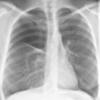

COPD

Date: 06/06/2004

Views: 14056